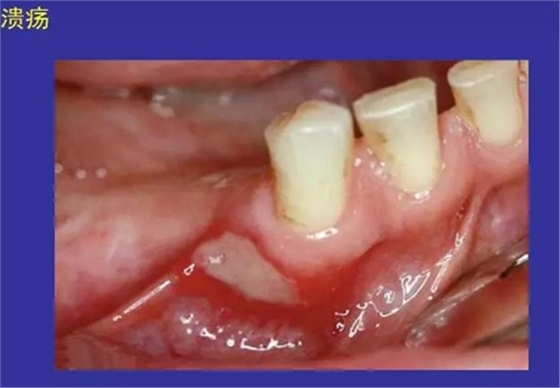

6.潰瘍:黏膜上皮的缺損或破壞而形成的凹陷

正??谇火つぜ俺R姴p圖